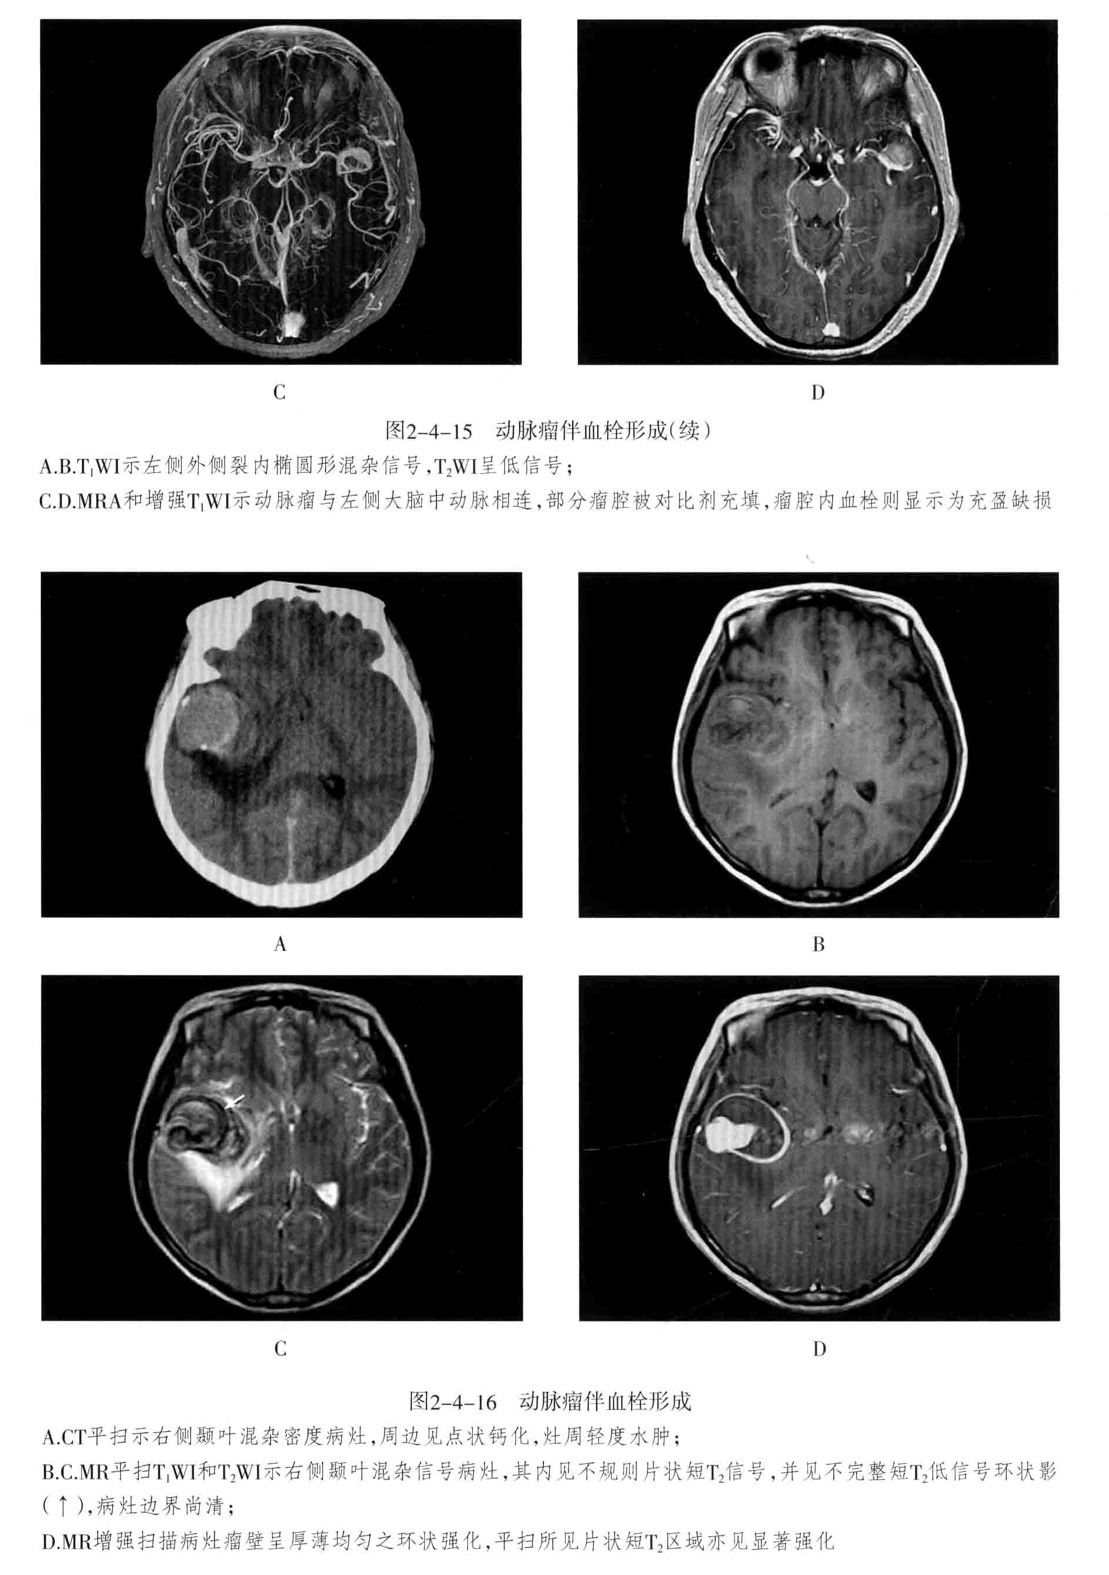

1. CT平扫为圆形高密度影,边缘清楚、增强有均匀强化,CTA或MRA可明确显示动脉瘤及其与载瘤动脉的关系。瘤样凸起。

2. 动脉瘤的瘤腔在T1WI、T2WI上均呈低信号,动脉瘤内有涡流时,也可产生轻微的不均质信号;瘤内血栓显示为高低相间的混杂信号。